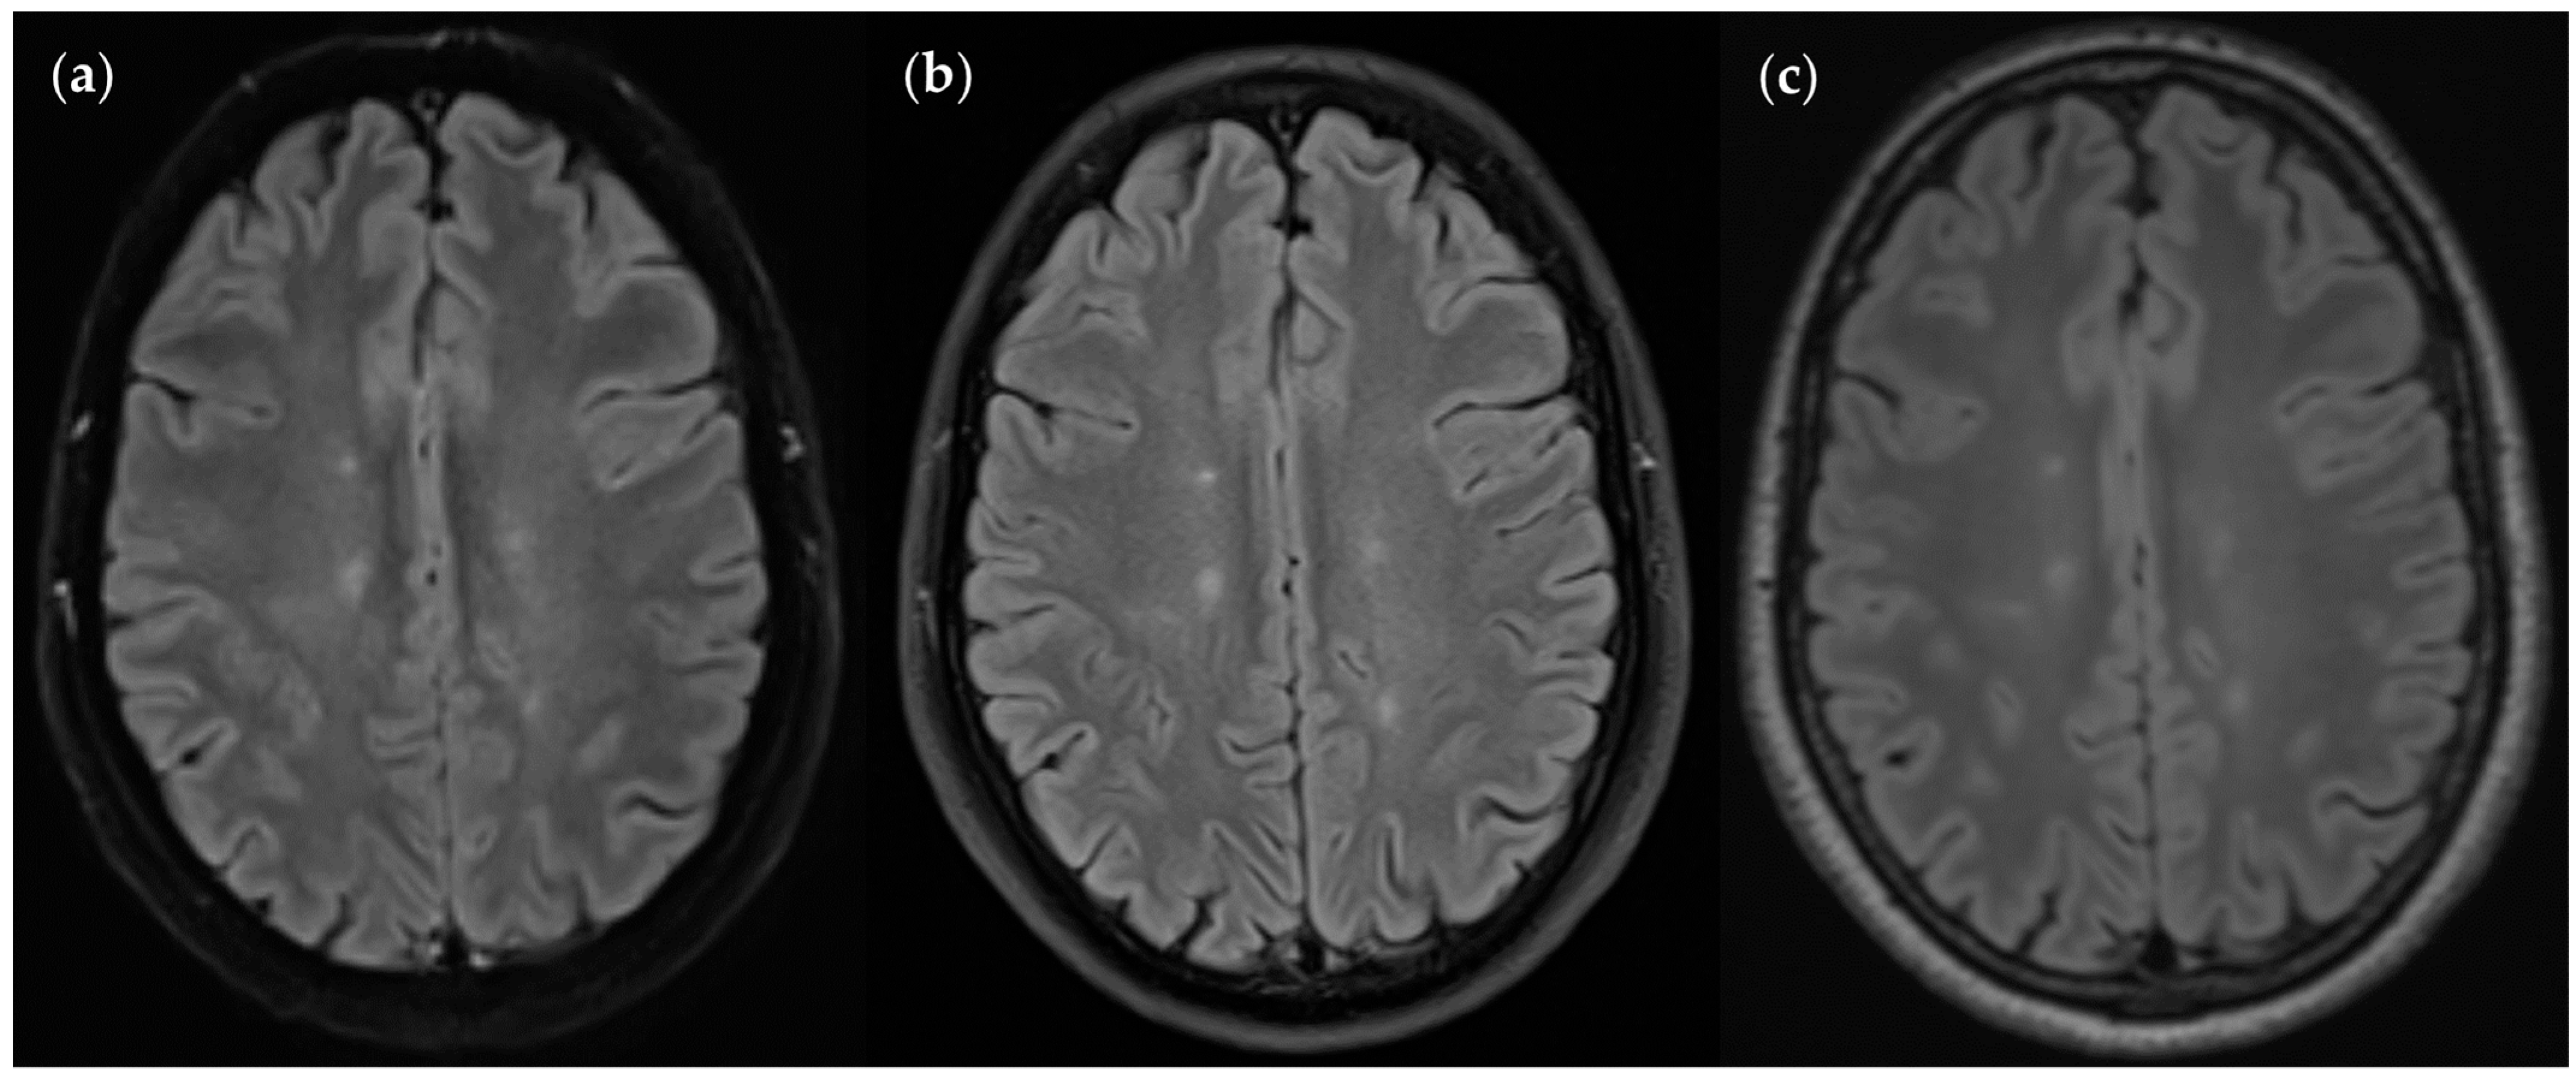

3.3. Image Quality

3.3.1. FLAIRUF Compared with FLAIR3Da

3.3.2. FLAIRUF Compared with FLAIRTSE

3.3.3. Positional Dependence of SNR and CNR in FLAIRUF

4.5. Outcomes Correlated with Technical Features